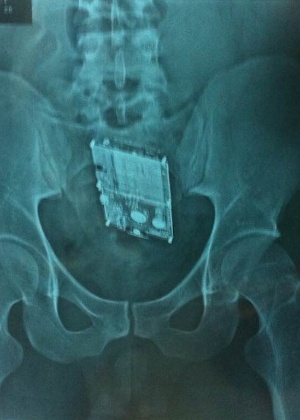

Um rapaz de 25 anos que cumpre pena por roubo, no presídio de Alfenas, em Minas Gerais, foi pego na segunda-feira, 19, com um smartphone no intestino. O aparelho foi descoberto durante revista de rotina nas celas, ocasião em que agentes penitenciários notaram que o detento, Flávio Martins Neto, estava meio estranho.

Com um detector de metais eles se aproximaram do preso, momento em que o equipamento acusou algo estranho em seu corpo. A Polícia Militar foi acionada e encaminhou o detento até o Hospital Universitário Alzira Velano, onde um exame de raio X confirmou a presença do celular.

Flávio Martins teve de ficar internado, mas não foi necessário cirurgia. Entretanto, foi preciso muito laxante para que ele expelisse o telefone da marca Apple. E, depois disso, teve de continuar no hospital para se recuperar antes de ser mandado de volta à cadeia.